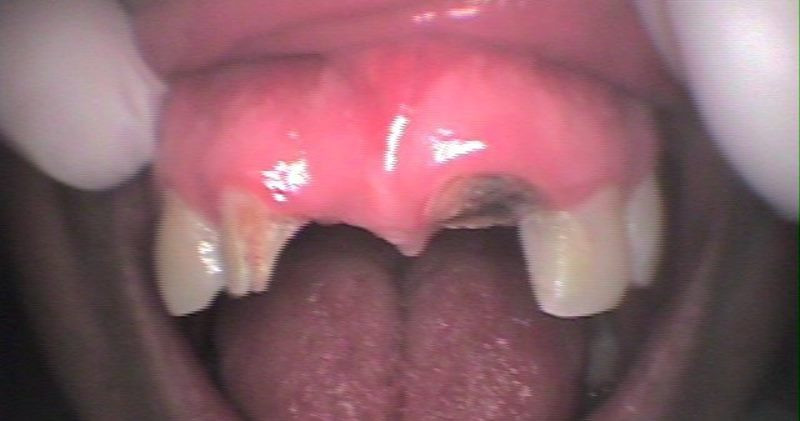

Caso Clínico Antes

Caso Clínico Después